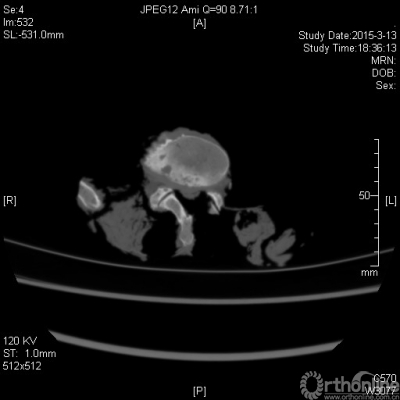

选取经福尔马林固定的完整无畸形无外伤成人脊柱区标本10具,在吉林大学中日联谊医院进行扫描。扫描后显示无病变(以上标本由延边大学基础医学院解剖学与组织胚胎学教研部提供);进行ULBD手术,术前术后分别通过320排螺旋CT(东芝320排Aquilion ONE )对脊柱标本进行编号并在骨窗下进行扫描。扫描厚度为2mm。对所有脊柱标本的腰椎节段进行了ULBD手术操作。共5个节段。对比不同层面椎管内容积变化,评估减压是否充分。

对脊柱标本进行CT扫描重建,术后CT如图3所示。分别选取三个层面:上终板层面,间盘层面,下终板层面,对术前、术后三个层面分别进行参数测量:椎管横径、椎管前后径、椎管面积。统计学分析结果:术后各层面参数均比术前增大,统计学差异有显著性。